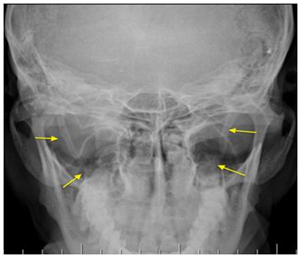

Standard radiology shows a continuation of the process by the styloid process of bone and a pseudo-joints appearance extending from the styloid apophysis at the small horn of hyoid (Figure 2).

Figure 2 Radiopaedia elongation of the styloid process

Figure2.Radiopaedia elongation of the styloid process.

The dental panoramic should be interpreted with caution due to high radiographic magnification level of the patient's inclination in the radio.